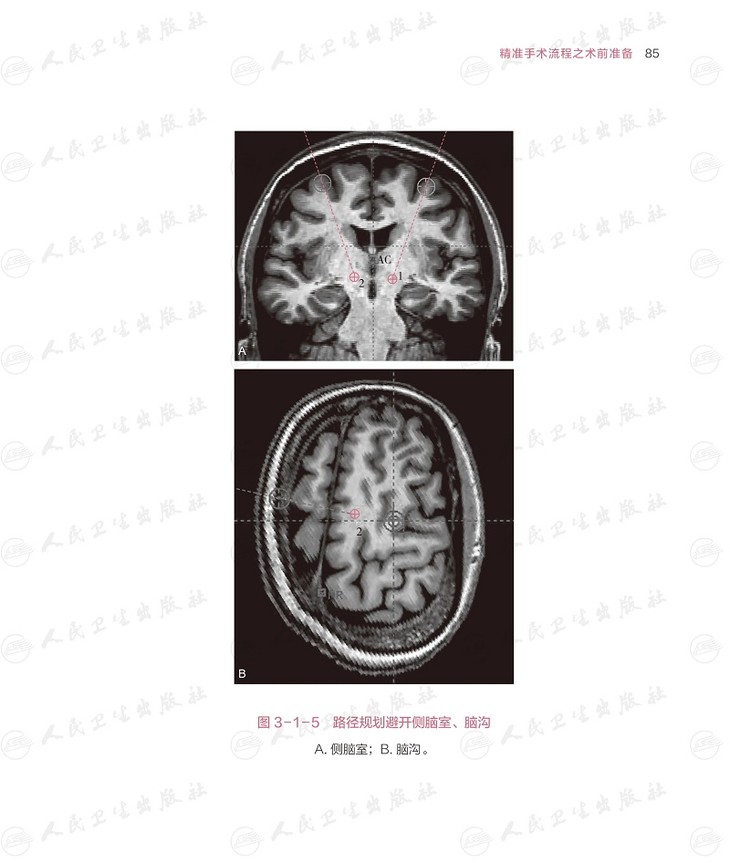

本书把帕金森病脑深部电刺激术相关的每个细节,从术前的评估,到包含两百余个步骤的手术过程,到程控的原理和方法,用形象的绘图,展示每个细节。本书的编撰凝聚了帕金森病脑深部电刺激术治疗领域 专家团队的心血,插图之精美,让人读来赏心悦目,学来受益匪浅。对于基层医生而言,本书无疑是提升专业技能、强化医患沟通意识的宝贵资源,值得细细研读。本书特联合国内比较有代表性的专家,以帕金森病为例,集各家所长,结合各大医院的方法,把精细的评估、精准的植入和个体化的程控做出 解读。